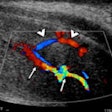

Imaging sheds light on complex cases of penile trauma